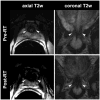

Methods and materials: This retrospective study included 108 men (median age, 64 years; range, 43-87 years) who received external-beam radiotherapy (EBRT) and/or brachytherapy for PCa and underwent endorectal-coil MRI of the prostate within 180 days before RT and a median of 20 months (range, 2-62 months) after RT. On all MRIs, two readers independently measured the urethral length (UL) and graded the margin definition (MD) of the urethral wall and the signal intensities (SIs) of the urethral wall and pelvic muscles on 4-point scales.

Results: The mean urethral length decreased significantly from pre- to post-RT MRI (from 15.2 to 12.6mm and from 14.4 to 12.9 mm for readers 1 and 2, respectively; both p-values <0.0001). Brachytherapy resulted in greater urethral shortening than EBRT. After RT, SI in the urethral wall increased in 57% (62/108) and 35% (38/108) of patients (readers 1 and 2, respectively). The frequency and magnitude of SI increase in pelvic muscles depended on muscle location. In the obturator internus muscle, SI increased more often after EBRT than after brachytherapy, while in the periurethral levator ani muscle SI increased more often after brachytherapy than after EBRT.

Conclusion: After RT for PCa, MRI shows urethral shortening and increased SI of the urethral wall and pelvic muscles in substantial percentages of patients.